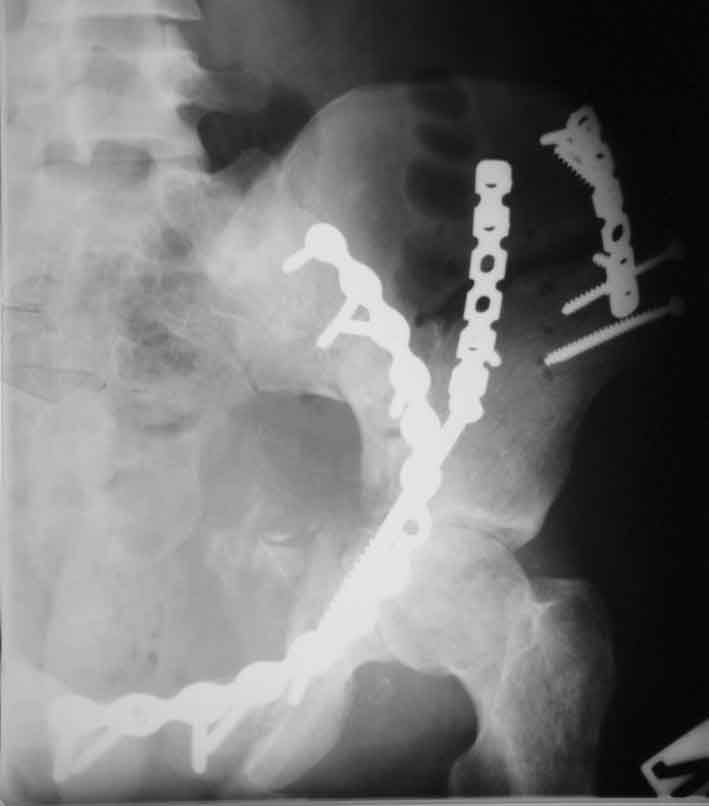

запирательная

По всей видимости, вы имеете в виду канюлированный винт, который проецируется на вертлужной впадине. Та вот, он проведен не через лонную, а седалищную кость. Вертлужная впадина абсолютно интактна. Это хорошо видно на проекции inlet.